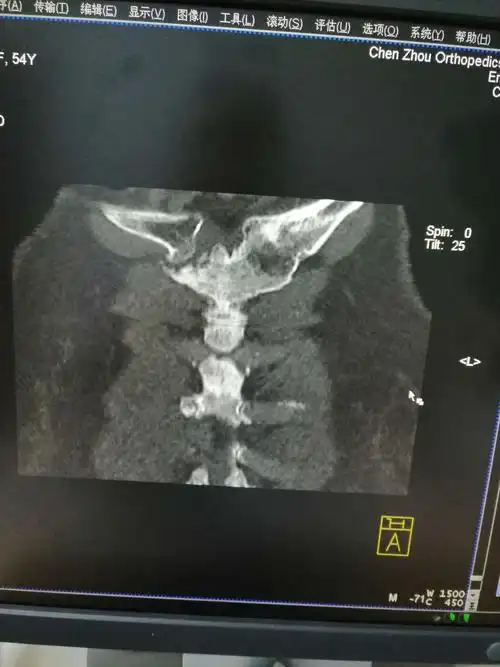

女性,54岁,胸骨柄突起畸形数年,偶尔疼痛

胸骨下压痛